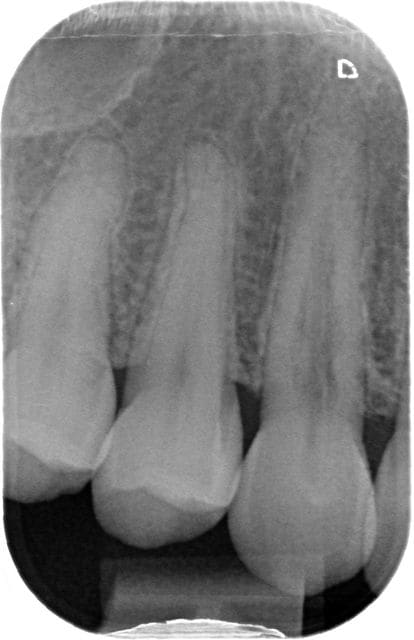

patiente 37 ans

dent asympomatique

radio 2011 et 2012